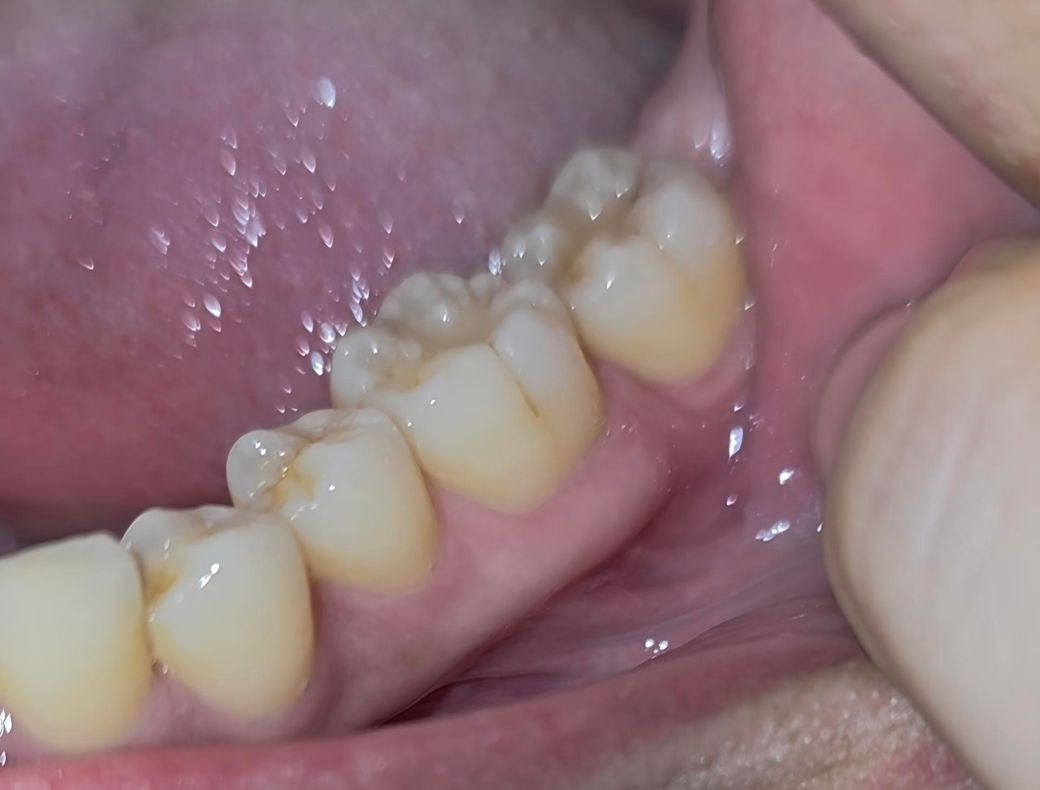

어금니 잇몸 퇴축 심한가요?? ?????

유독 맨끝 어금니쪽 워터픽으로 하면 아픕니다. 혹시 잇몸퇴축이 심한가요?? 최근에 잇몸치료했는데 별말씀없긴했어요 ㅠㅠㅠㅠ

잇몸퇴축이 심한 편은 아닙니다. 다만 큰어금니 2개끼리 단차가 있어 다른 부분에 비해서 비교적 음식물이 잘 끼이고, 닦기도 쉽지 않아 잇몸이 좀 더 잘 붓는 것 같습니다. 워터픽보다는 치실이나 치간칫솔 등 직접적으로 음식물과 치태를 제거할 수 있는 용품을 사용하시면 좋을 것 같습니다.

맨끝 치아의 잇몸퇴축이 있지만 심해 보이지는 않습니다. 워터픽의 수압을 낮춰서 사용하는것을 권유드립니다. 건강하세요.

잇몸 퇴축은 그닥 심하지 않습니다